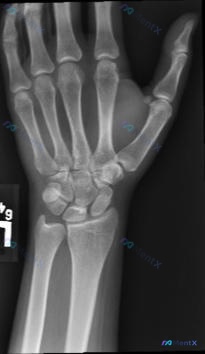

大家好,今天遇到一份左手腕关节正位(PA)X光片。影像分析显示:桡骨远端、尺骨远端及所有腕骨骨皮质连续,未见明确骨折线;桡腕关节、下尺桡关节及腕中关节对位良好,间隙正常;骨质密度均匀,无溶骨性破坏或占位;腕周软组织清晰,无肿胀或异物。 但临床背景需要注意:如果患者有明确的外伤史,或者持续腕部疼痛、功...

整理到一份左侧腕关节正位X光片的影像分析资料,想和大家讨论下这类情况的临床思路。 影像表现梳理: - 腕骨(舟骨、月骨、三角骨等)序列、形态大致正常,未见明确骨皮质中断或错位;桡骨远端、尺骨茎突、掌骨基底部也未见明确骨折线。 - Gilula三条弧线走行光滑连续,舟月间隙、月三角间隙未见明显增宽;桡...

整理了一个很有启发性的运动损伤病例,核心在于「不要被正常的静态X光片带偏」。 --- 病例资料 - 患者:22岁女性体操运动员 - 病史:左手腕疼痛不适1个月,有韧带病史,已接受手腕保守治疗 - 影像(X光正侧位): - 桡骨远端、尺骨远端、腕骨群骨质完整,未见明确骨折线、脱位或骨质改变 - 桡腕关...